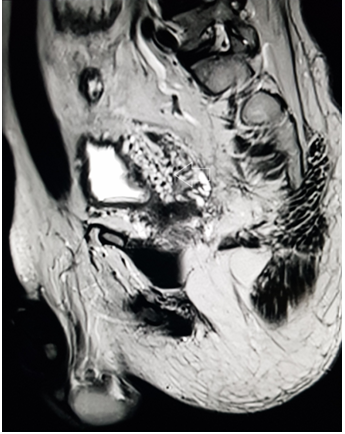

A 39 year old male presented with the chief complaint of pelvic discomfort and on and off haematuria. It was not associated with fever or urinary retention. No bowel symptoms were noted. Patient had history of paralytic poliomyelitis in his childhood and walked with crutches. On laboratory examination, patient was found to have deranged renal function tests with elevated creatinine level. Hence, we conducted MRI pelvis with MR urography to look for the urinary systemand to look for the status of the the pelvic muscles and joints. MR study showed multiple tortuous dilated vessels on the right side of pelvis suggestive of pelvic arteriovenous malformation (Figure 1&2). The arterial supply was noted from multiple branches of the right internal iliac artery and venous drainage was noted into right external iliac vein and deep external pudendal vein. The tangle of vessels was abutting the right lateral wall of urinary bladder, prostate and right seminal vesicle medially (Figure 1&3). It was abutting the obturatorinternus muscle laterally. There wasasymmetric thickening of the right lateral wall of urinary bladder adjacent to the vascular malformation (Figure 1). It was not associated with perivesicular fat strandings or enlarged locoregional lymphnodes. No restriction of diffusion was noted in DWI images. Prostate and bilateral bilateral seminal vesicles were normal in signal intensity and morphology. As a sequalae of childhood poliomyelitis, diffuse atrophy of pelvic muscles was noted that was more prominent on the right side (Figure 4&5). T1 and T2 high signal intensity suggestive of fatty replacement was noted in bilateral psoas and right obturaterinternus mucle. Fatty atrophy of bilateral hip and proximal thigh muscles were also seen (Figure 5). Abduction and external rotation was noted at bilateral hip joints (Figure 4). Histological examination of the bladder wall revealed polypoid bladder mucosa with chronic inflammation consistent with polypoid cystitis. Arteriovenous malformation was managed with intra-arterial coil embolization and subsequently the patient’s symptoms improved.

Figure 1 MRI axial T2 weighted image through the pelvis demonstrate multiple tortuous vessels (white arrow) on the right side extending to the right lateral wall of urinary bladder. The vessels are dilated and show loss of signal suggestive of high flow vascular malformation. Associated mild thickening of right lateral wall of urinary bladder is also noted (black arrow).